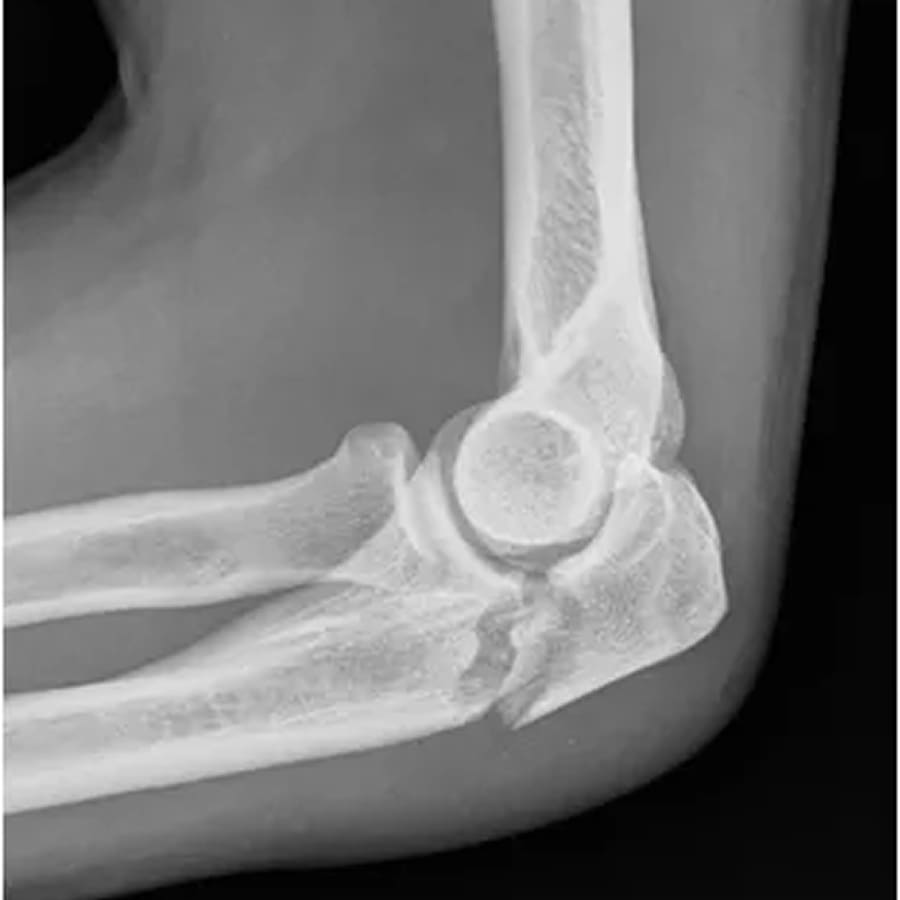

A fratura de cotovelo ocorre quando um ou mais ossos que compõem a articulação (úmero, rádio e ulna) sofrem ruptura. Essa região é fundamental para os movimentos, o que torna a lesão especialmente delicada. Entre as mais comuns estão:

- fratura da cabeça do rádio;

- fratura do olécrano;

- fratura do úmero distal;

- fraturas combinadas.